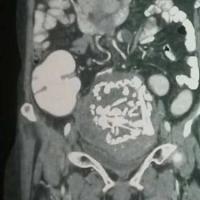

Kết quả X-quang phát hiện trong ổ bụng bệnh nhân Lục có một dị vật. Chính dị vật này đã đâm thủng thành manh tràng và gây viêm manh tràng.

Kết quả X-quang phát hiện trong ổ bụng bệnh nhân Lục có một dị vật. Chính dị vật này đã đâm thủng thành manh tràng và gây viêm manh tràng. Hiện bệnh nhân khá tỉnh táo, các bác sĩ sẽ mổ sớm để lấy dị vật trong ổ bụng ông Lục.